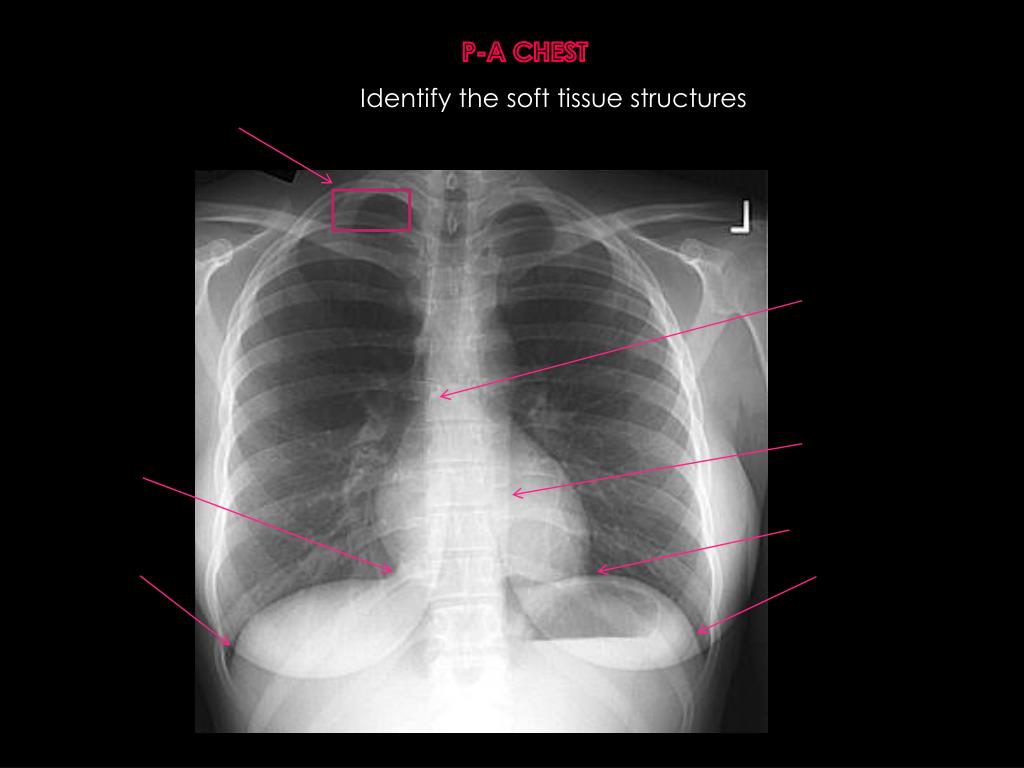

5. P-A CHEST Identify the soft tissue structures

6. P-A CHEST Identify the soft tissue structures Tracheal air shadow Lt main stem bronchus Aortic Knob Lt ventricle Rightatrium Magenblasse Right hemidiaphram Breast shadow

7. P-A CHEST Identify the soft tissue structures

8. P-A CHEST Identify the soft tissue structures Right lung apex Carina Descending thoracic aorta Rightcardiophrenic angle left Cardiophrenic angle Right costophrenic angle Left costophrenic angle

9. P-A CHEST Identify the soft tissue structures

10. P-A CHEST Identify the soft tissue structures left hilum RightHilum Pulmonary vessels (bronchovasicular markings)